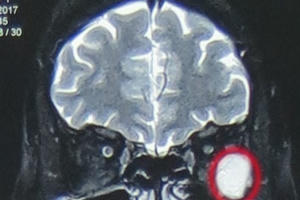

Theo thông tin từ Bệnh viện Hữu nghị Việt Đức (Hà Nội) ngày 31/10, cơ sở này tiếp nhận một nạn nhân trong vụ tai nạn ở Lạng Sơn được chuyển từ bệnh viện tuyến dưới.